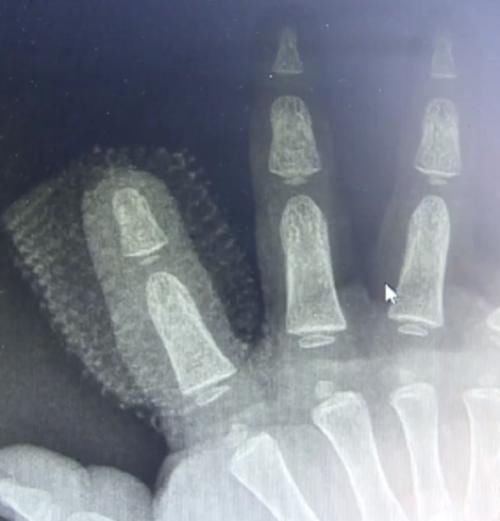

【 兔子|1岁男童被兔子咬断手指,家人杀兔取指为时已晚,表示3天没喂过】据了解,天天的家中养了一大一小2只兔子,还有几只鸡,在事发前几天家中人因为有事就没有给兔子喂食,在办完事情回家之后,天天就自己跑到兔笼前玩。但没多久就听见孩子大哭的声音,家人跑过来一看,只见其右手鲜血直流。一家人着急忙慌的带孩子去医院,医生发现天天右手食指少了一截,家人又回家找,最终将兔子给杀了,在其身体里取出断指,遗憾的是只发现了一点,断指已经不能用了,可能是被咀嚼、消化了一部分。

随后,天天在当地医院进行简单的包扎之后,走到博爱医院,经钟医生等人紧张的手术,最终,天天顺利离开了手术室。目前,手指恢复良好,保住了关节,对以后写字等都不会有太大的影响。事情还是十分的遗憾,毕竟孩子还那么小,这也告诫广大家长朋友,在照顾孩子时一定要注意,不要造成不可挽回的损失。